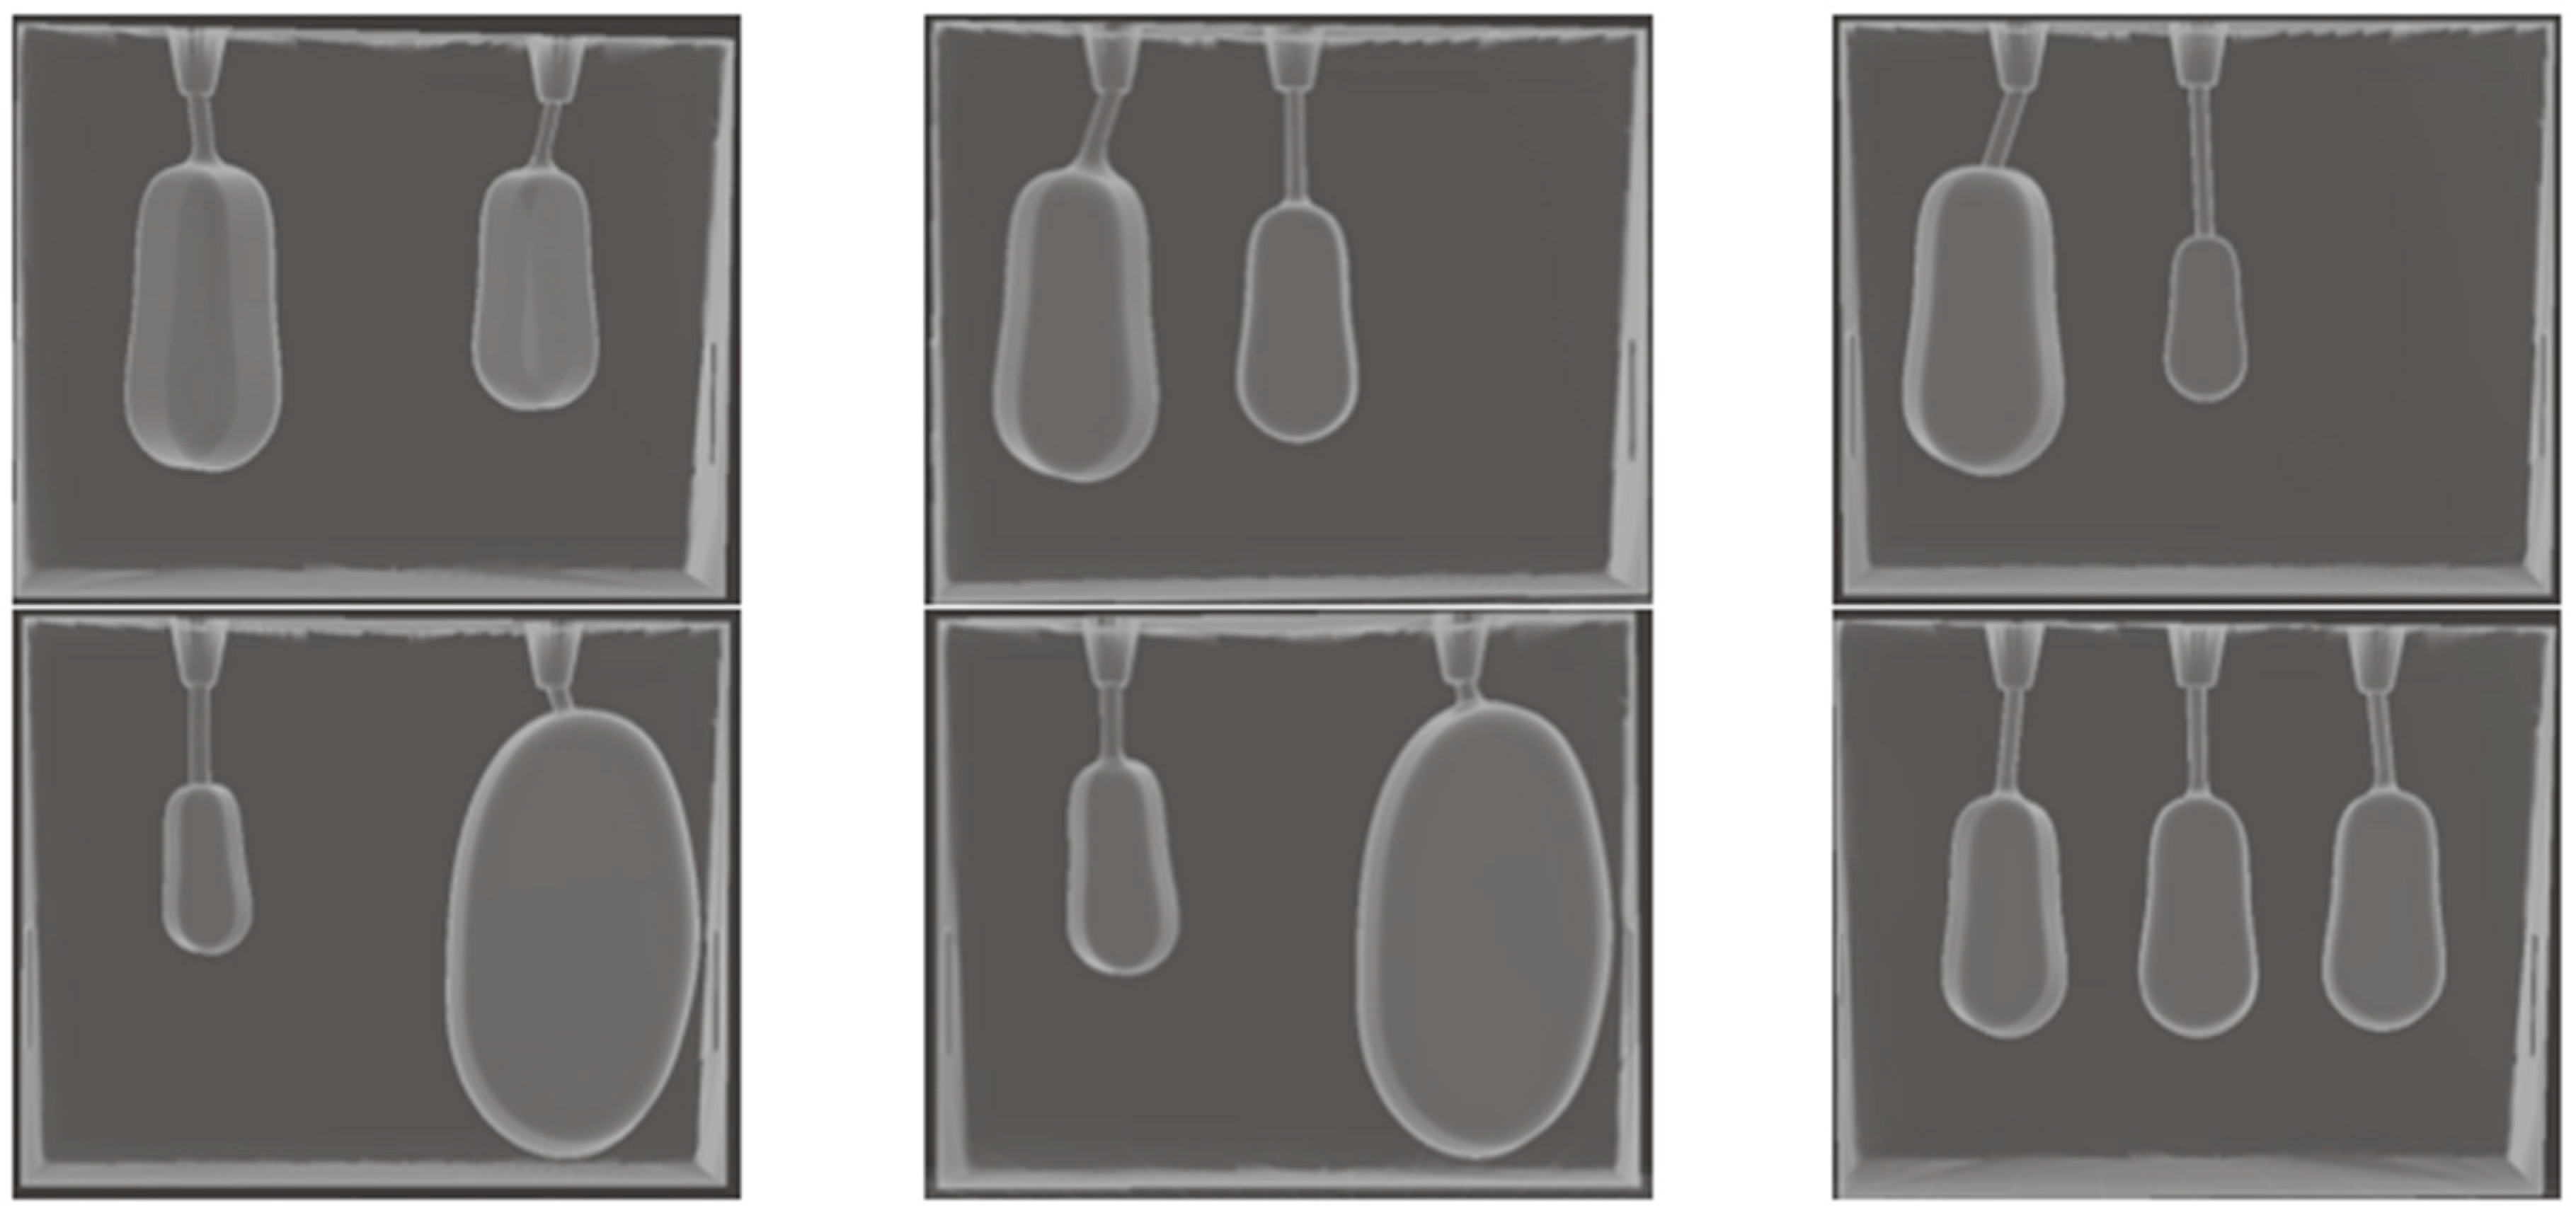

Six sections (7 × 5 × 1.5 cm3) with two or three hollow cavities (thyroid remnants) of different sizes (0.5–10 mL), at clinically relevant positions after thyroidectomy, were designed as shown in Figure 3 and Figure 4. Each section can be easily added and removed from the front outer hollow cavity of the phantom, as shown in Figure 1. The section width was separated into three equal-sized areas as shown in Figure 3a. A remnant was horizontally and vertically centered in an area. The left and right remnants were rotated by 30° to fit into a section. Tiny openings were drawn at the top of a section to inject diluted radiopharmaceuticals into the hollow cavities of the remnants.

Figure 4. The designed sections with thyroid remnants of: (top-left and top-middle) 3 and 1.5 mL at different positions, (top-right) 3 and 0.5 mL, (bottom-left) 0.5 and 10 mL, (bottom-middle) 1 and 10 mL, and (bottom-right) 1.5 mL each.